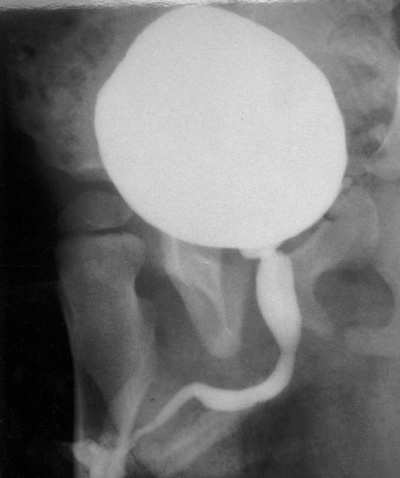

Válvula de uretra posterior

Folheto membranoso dentro da uretra posterior (uretra prostática) funcionando como válvula, obstruindo saída da urina

Clínica: distensão vesical e jato urinário fraco

Tratamento: sondagem pós natal, cirurgia

EMERGÊNCIA MÉDICA